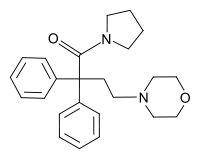

Beta-Amino Ketones

Diphenylmethylpiperazines